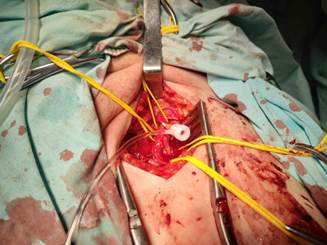

В ходе операции выполнен разрез по линии Кена в верхней трети левого бедра. Выделены ОБА, ПБА и ГАБ. В ОБА пальпировалась циркулярная атеросклеротическая бляшка. Была выполнена продольная артериотомия ОБА c переходом на устье ГАБ. Выполнена эндартерэктомия из ОБА. Решено произвести профундопластику заплатой для расширения устья ГАБ. В качестве пластического материала использован участок ствола большой подкожной вены, резецированный из этого же доступа и реверсированный. Пластика аутовенозной заплатой нитью 6/0. Пуск кровотока. В участок передней стенки ОБА выше места заплаты был установлен интродьюсер 7 фр. (рис. 2). При ангиографии визуализирована окклюзия ОПА на протяжении. После проведения мягкого гидрофильного проводника установлен баллон со стентом Balton Neptun 10 на 60 мм, выполнена ангиопластика и стентирование ОПА (рис. 3 и 4). На контрольной ангиографии восстановление просвета ОПА (рис. 5). Зафиксировано появление четкой пульсации артерий в ране. В месте доступа наложен боковой шов на ОБА. Послойные швы на рану до активного дренажа. Кровопотеря за время операции до 100 мл.

Рис. 2. Выполнены эндартерэктомия из ОБА, пластика аутовенозной заплатой,

установлен интродьюсер в ОБА